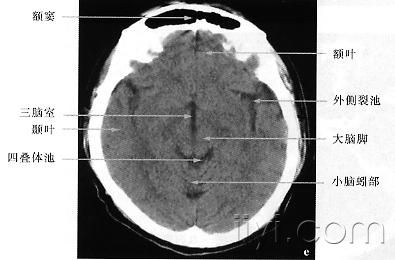

正常头部ct图谱